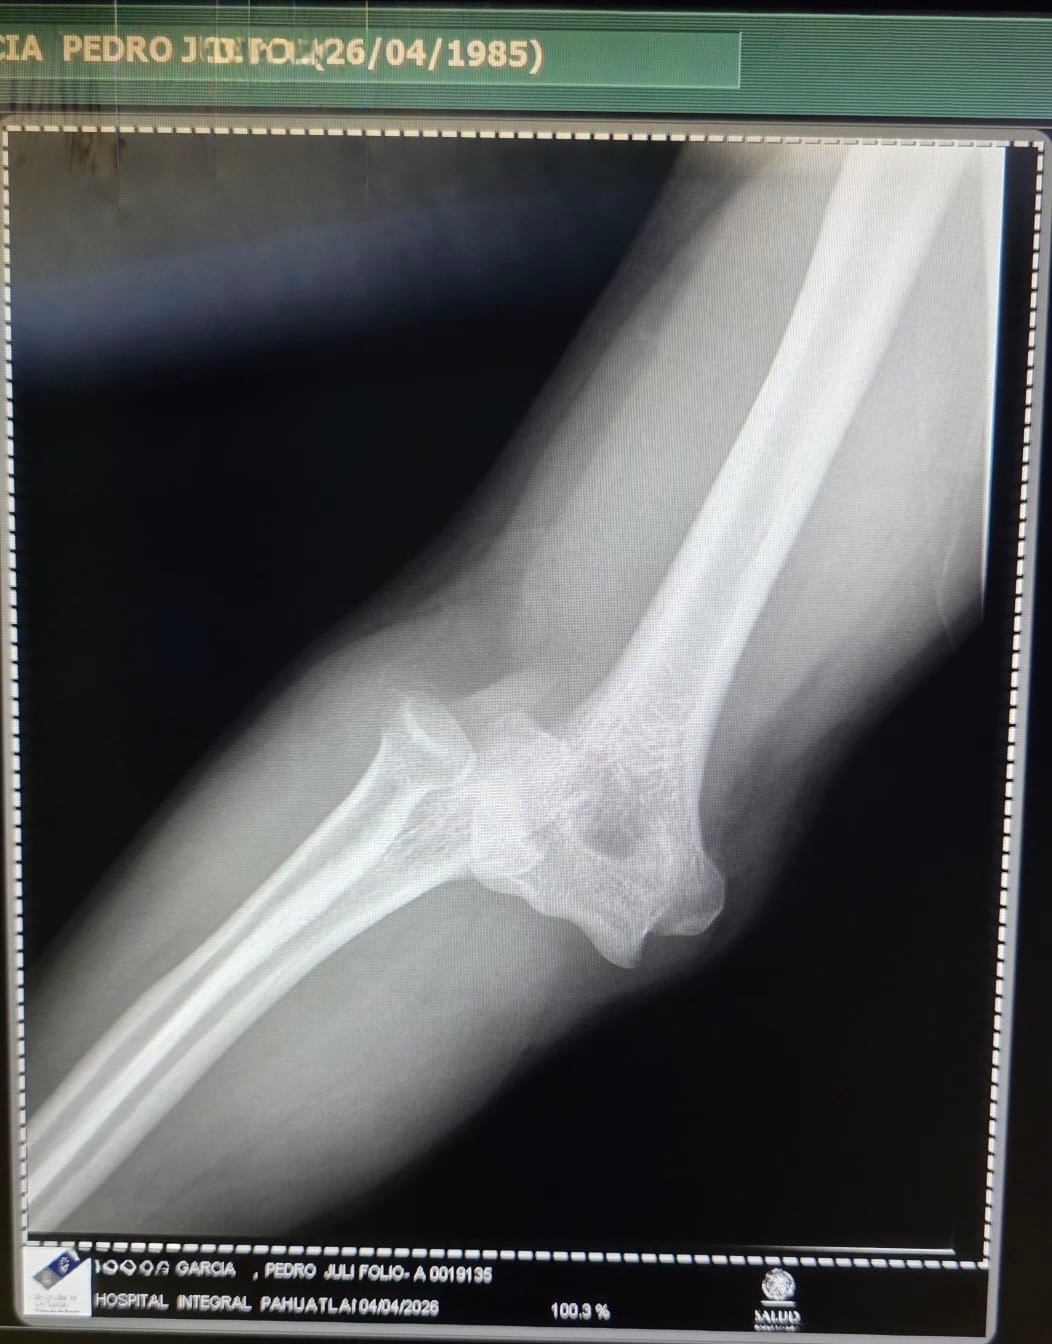

El día sábado sufrí una caída dislocándose mi codo derecho de una manera muy complicada para poder acomodarlo, tuve que viajar más de 5 hrs para poder encontrar atención médica capacitada para que realizaran la reducción (acomodo del hueso) pero al hacerlo se produjeron 2 fracturas, hasta hoy la cuenta médica asciende a $190,000 y sumando, ayúdenme a salir de esto.